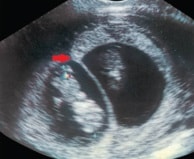

amniotic